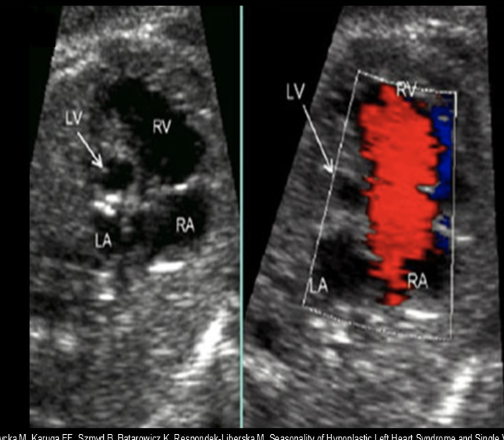

while scanning the 4 chamber heart view, you see an enlarged right heart w/very small left ventricle + atrium. you move to the LVOT view and the ascending AO is much smaller than normal

.

a) marfan syndrome

b) pulmonary HTN

c) Ebstein anomaly

d) hypoplastic left heart